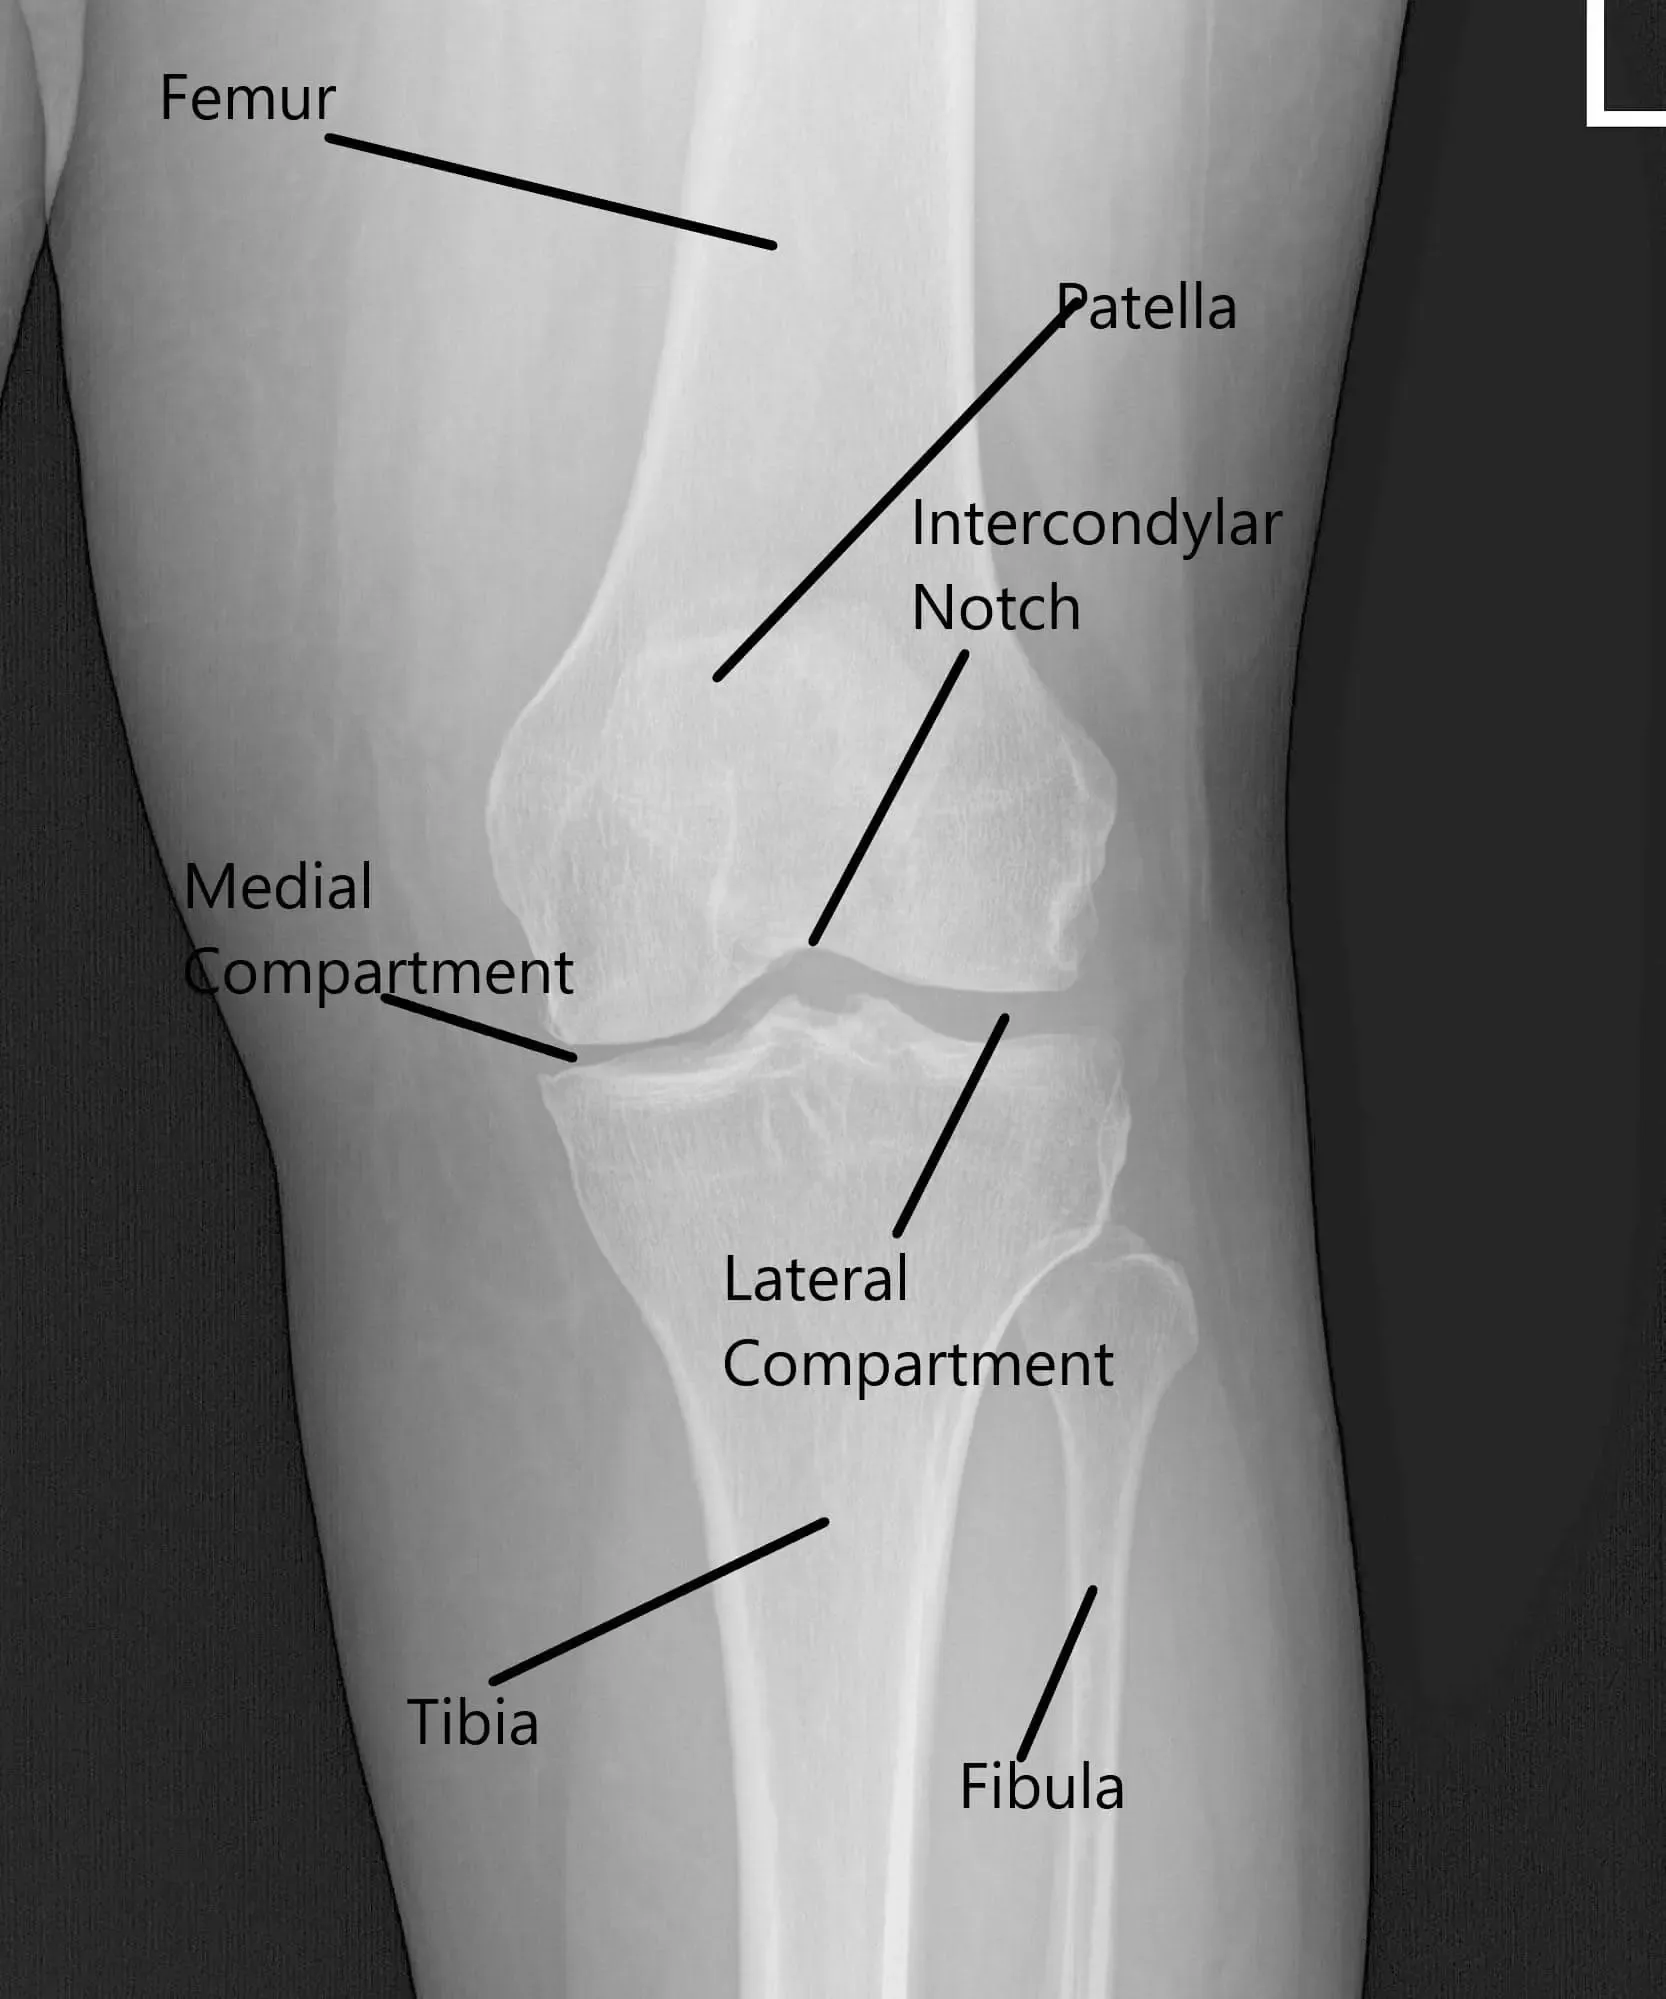

Radiografía de la rodilla izquierda que muestra las vistas AP y lateral.